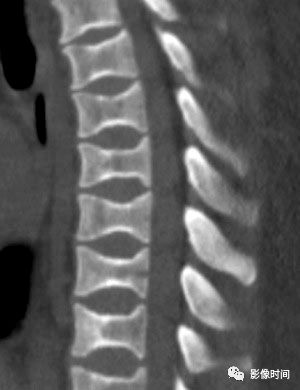

29鱼椎

鱼椎(Fish vertebra),又称鳕鱼椎(codfish vertebrae)

所谓鱼椎是指椎体上下终板双凹导致的椎体形态改变,与鱼类椎体(双凹)形态相似而得名。这种凹陷是平滑的,与 H 型椎体的凹陷边界相对截然的不同。本征象通常用于描述成骨不全的椎体改变,但也可以见于骨质疏松症、肾性骨病、骨质软化、高胱氨酸尿症等疾病。

病例 1,1 岁男孩,成骨不全。腰椎侧位片示椎体密度减低,多发椎体双凹畸形,呈「鱼椎」样。

病例 2,骨质疏松症。CT 矢状位骨窗示椎体密度减低,骨小梁稀疏,多发椎体「鱼椎」样双凹变形。